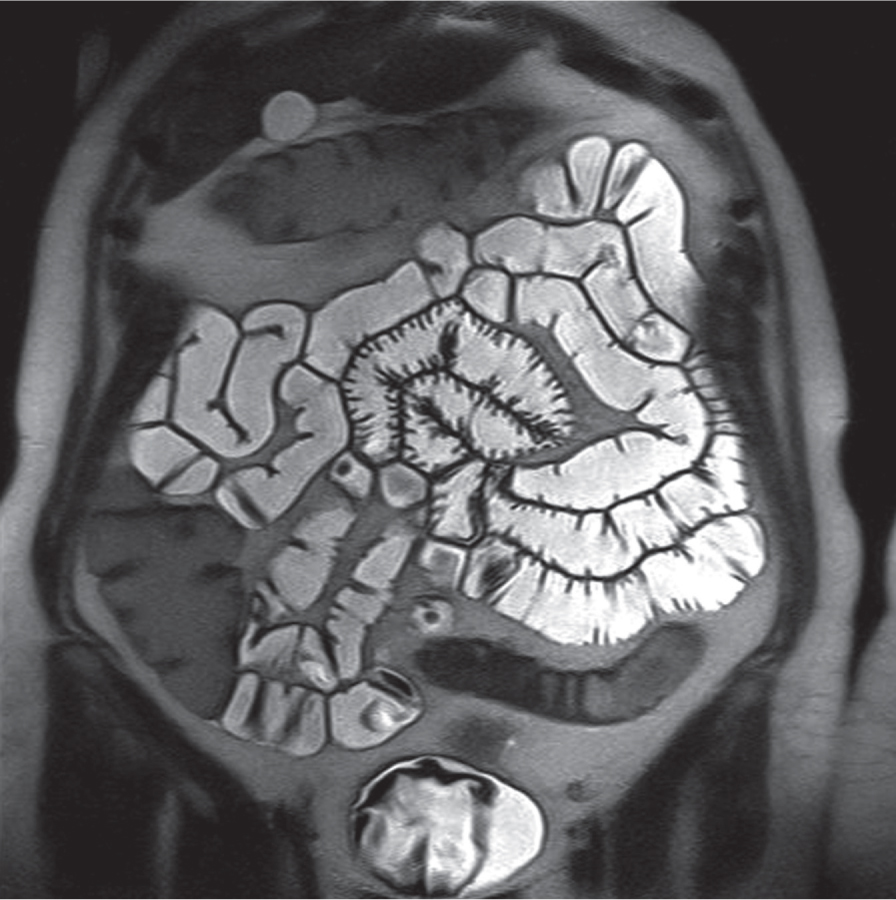

Enteroklizis

İnce bağırsağın renklendirici (Baryumlu) madde ile yıkanıp görüntülenmesi işlemidir. (Bkz; Enter-o-klizis)

Bu muayene için hastanın muayene günü ayık olması (yemek yememesi, içmemesi, sigara içmemesi) önemlidir. Gerçek muayeneden önce, bir tüp burundan ince bağırsağa (nazojejunal sonda) itilir. Suda çözünmeyen baryum sülfat, X ışını pozitif kontrast ortamı olarak uygulanır. Daha sonra, baryum sülfatı ince bağırsağın geri kalan kısmına iten ve bağırsak duvarlarının birbirine yapışmasını önleyen sulu metil selüloz (X-ışını negatif kontrast maddesi) uygulanır. Bu çift kontrast, bağırsak lümeninin şeffaf görünmesini ve bağırsak duvarlarının baryum sülfat birikimi ile incelenmesini sağlar. Muayene genellikle 30-45 dakika sürer.